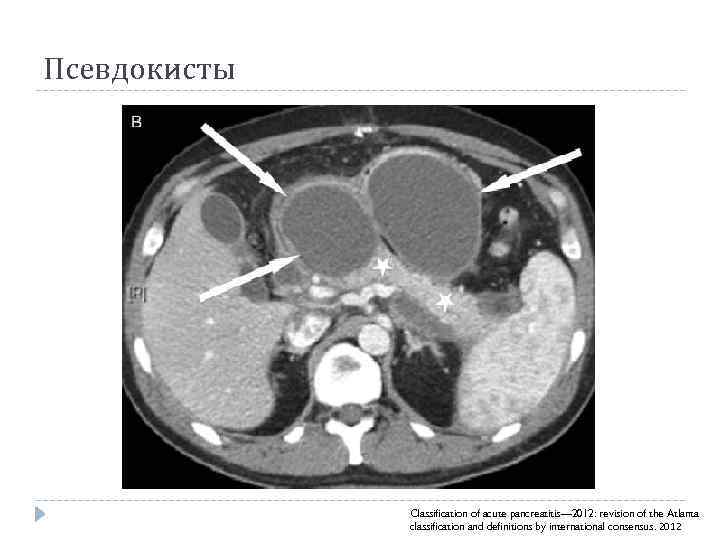

Псевдокисты Classification of acute pancreatitis— 2012: revision of the Atlanta classification and definitions by international consensus. 2012

Псевдокисты Classification of acute pancreatitis— 2012: revision of the Atlanta classification and definitions by international consensus. 2012